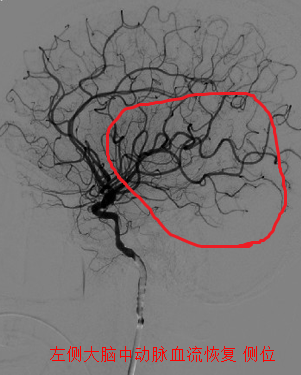

取栓后患者血管再通

刘忠锦副院长带领神经介入小组迅速到达导管室,20分钟后诊断造影确认患者为左侧颈内动脉末端闭塞,47分钟后患者血管内栓子取出,血管再通,前向血流mTICI3级。在神经内科、急诊医学科,导管室和麻醉科通力合作下,手术顺利完成,病人术后复查头CT后送往重症监护室,病情平稳后转回神经内科五病区病房。术后一周,患者脑部功能完全恢复。